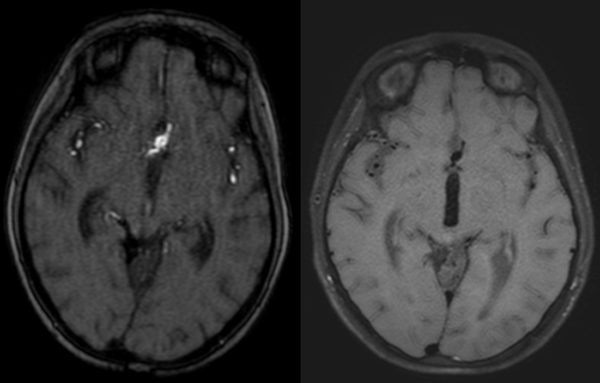

Dos años más tarde, en control por Infectología, refirió cefalea holocraneana pulsátil de moderada intensidad, asociada a mareos, náuseas y vómitos esporádicos. Se solicitó una nueva angioRM, la que arrojó un aneurisma fusiforme de la arteria comunicante anterior con compromiso del segmento A2 izquierdo e irregularidad asociada de M1 derecho (Figuras 3 y 4). Ante estos hallazgos se efectuó angiografía cerebral con colocación de un diversor de flujo, angioplastia con balón y embolización con “coils”.

Figura 3. RM cerebral, secuencia blackblood: dilatación aneurismática de 8.1 x 5.9 mm en el segmento comunicante anterior e irregularidad con reducción de calibre en M1 derecho. La técnica suprime la señal de la sangre en movimiento, haciendo que la luz vascular se observe negra y permitiendo resaltar la pared arterial.